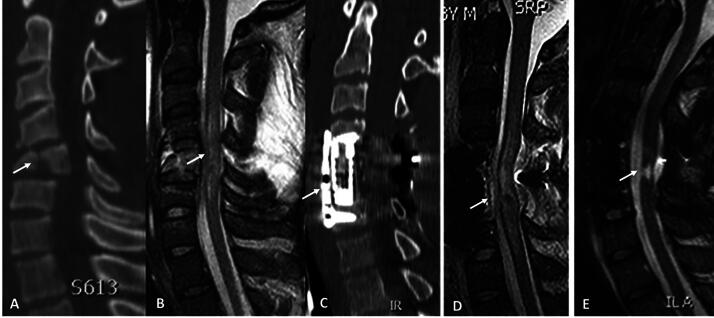

脊髓损伤(SCI)仍然是一个主要的未解决的问题,它永久性地损害了全世界无数人的生命。尽管SCI的基础、临床前和临床科学的进步为患者带来了希望,但临床医生可能缺乏对相关细胞和分子事件的全面了解,实验室研究人员可能低估了细胞和分子现象如何转化为有意义的功能结果。为了帮助弥合这些观点,我们首先回顾了美国脊髓损伤协会(ASIA)损伤量表(AIS)分级,这是衡量脊髓损伤临床结果的主要工具,以及临床上重要的AIS分级“转换”(改善)概念,这发生在一些但不是所有患者身上。然后,我们回顾了导致AIS分级及其转化的潜在机制,包括短暂性神经功能障碍机制(神经元和轴突“昏迷”)、继发性细胞损失机制(凋亡、焦亡和坏死)和轴突损失机制(原发性轴突切断和继发性轴突变性)。最后,我们简要回顾了可能改善脊髓损伤后继发性组织损失和神经功能障碍机制的临床治疗方法。

Spinal cord injury (SCI) remains a major unsolved problem that permanently impairs the lives of innumerable individuals worldwide. Although advances in the basic, pre-clinical and clinical sciences of SCI hold promise for patients, clinicians may lack a full insight into the relevant cellular and molecular events, and laboratory researchers may underappreciate how cellular and molecular phenomena translate into meaningful functional outcomes. To help bridge these perspectives, we first review the American Spinal Injury Association (ASIA) Impairment Scale (AIS) grade, which is the principal instrument used to gauge clinical outcomes in SCI, and the clinically important concept of AIS grade "conversion" (improvement), which occurs in some but not all patients. We then review underlying mechanisms that contribute to the AIS grade and its conversion, including mechanisms of transient neurological dysfunction (neuronal and axonal "stunning"), mechanisms of secondary cell loss (apoptosis, pyroptosis, and necroptosis), and mechanisms of axonal loss (primary axotomy and secondary axonal degeneration). Finally, we briefly review approaches to clinical management that may ameliorate identified mechanisms of secondary tissue loss and neurological dysfunction following SCI.